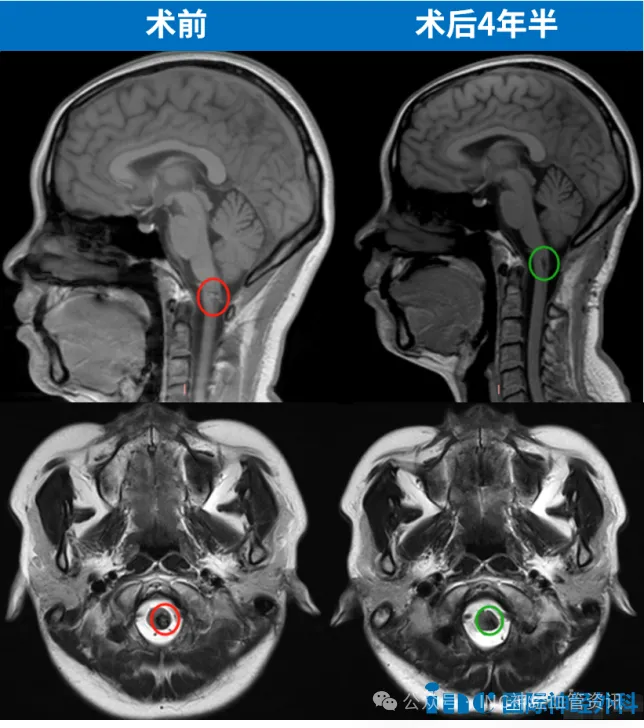

术后第十二天,王女士出院了。术后MRI显示病变得到全切,困扰她四年的脑血管疾病终于被彻底摆脱。